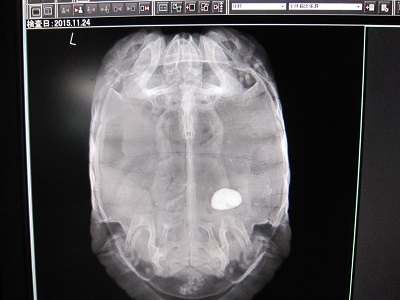

そのカメは、昨年の秋に体調を崩し、治療した際にレントゲンを撮ったところ、膀胱に結石がありました。

それがコチラの写真です。

そこで、そのカメのレントゲンを撮ってみたところ、

結石がなくなっているではありませんか!

やはりこのカメが出した結石のようです。